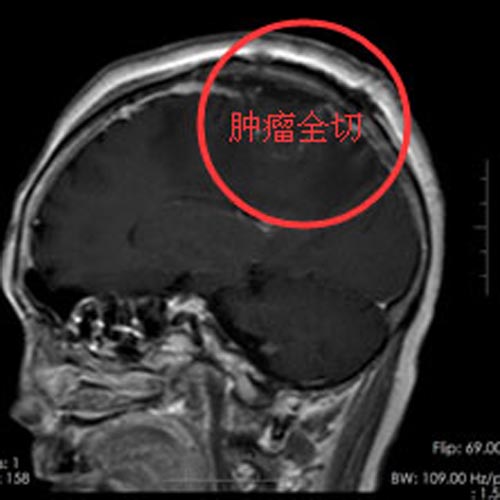

取得家属支持后,阿婆在全麻下行“左侧额顶部占位病变切除术”,术中可见肿瘤位于右额顶交界处,大小约3cm×4cm×3cm,将肿瘤全切除,术程顺利。术后的余阿婆恢复良好,肢体活动恢复正常,头痛头晕症状消失。

▲手术后